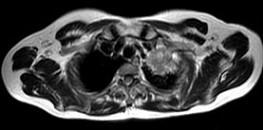

问题 男,68岁,声音嘶哑半月,行MRI检查如图,其最可能的诊断为 ( )

选项 A、左上肺癌 B、左上肺动静脉瘤 C、左上肺结核球 D、左上肺炎性假瘤 E、右上肺癌

答案 A